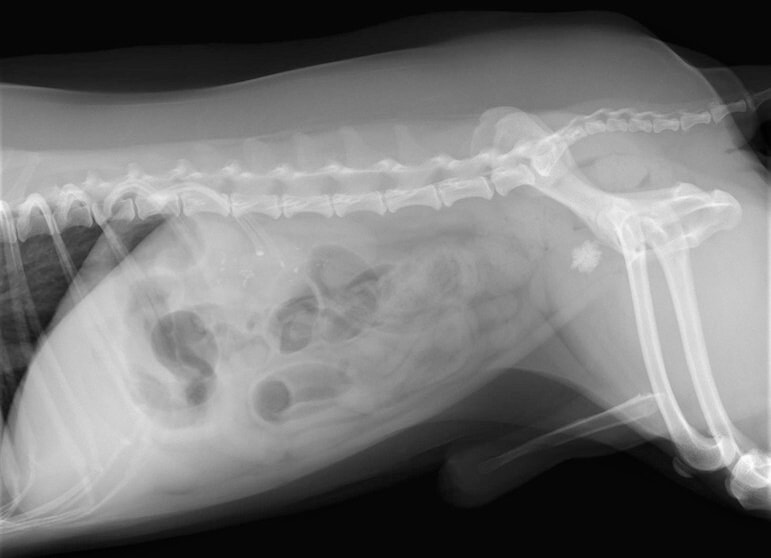

術前レントゲン

腹部臓器が胸腔内に脱出し、腹部と胸部の境界および心臓や肺の陰影が不明瞭になっています。また、胸腔内に消化管のガス陰影が認められます。